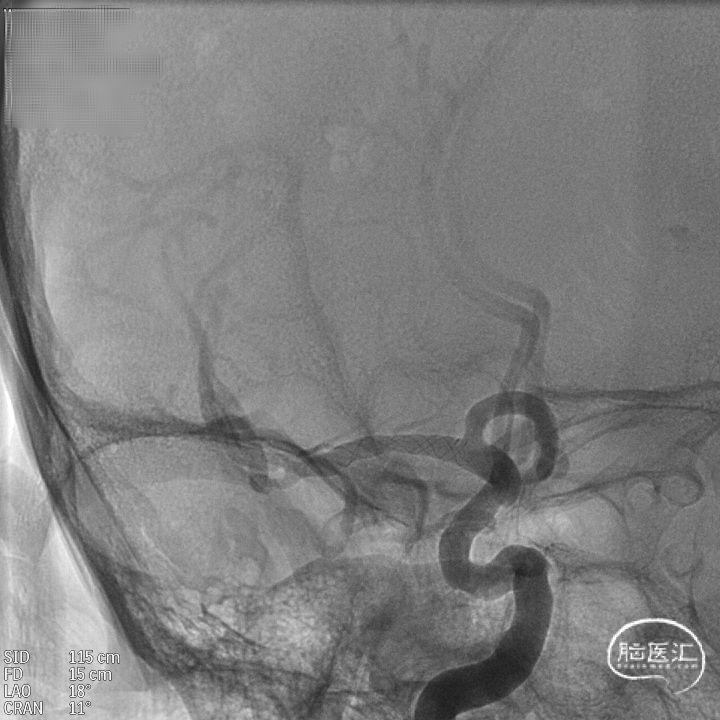

术后造影:支架充分覆盖动脉瘤瘤颈,贴壁良好,瘤体内可见造影剂滞留。

术后支架显影:定位精准,未覆盖颞前动脉及大脑前动脉。